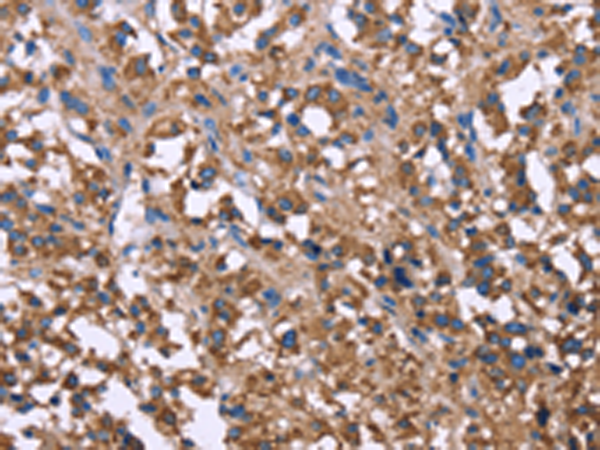

分类: 科研抗体货号: P10641别名: ACEH应用: IHC反应种属: Human, Mouse, Rat